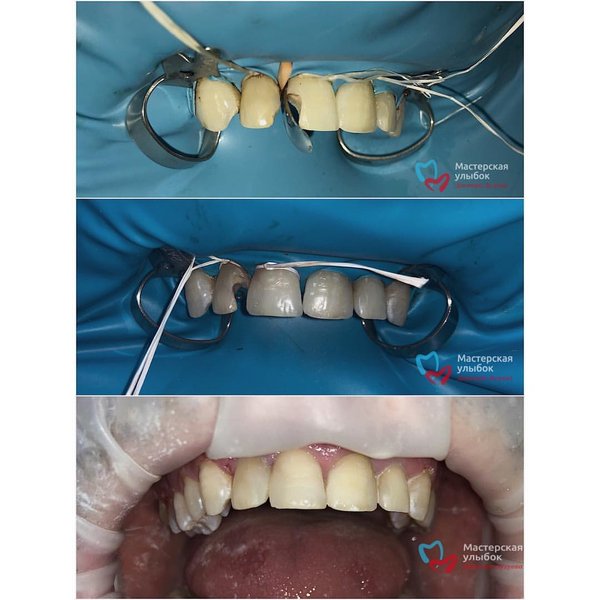

Реставрация передних зубов. В случае с фронтальной группой зубов данную потерю тканей необходимо всегда по возможности минимизировать, чтобы достичь максимального сохранения здоровых тканей зуба ️, а значит, и естественной эстетики. . Врач: Лугуев Арслан . ул.Абубакарова 98 (Чернышевского). Тел. для записи: ️